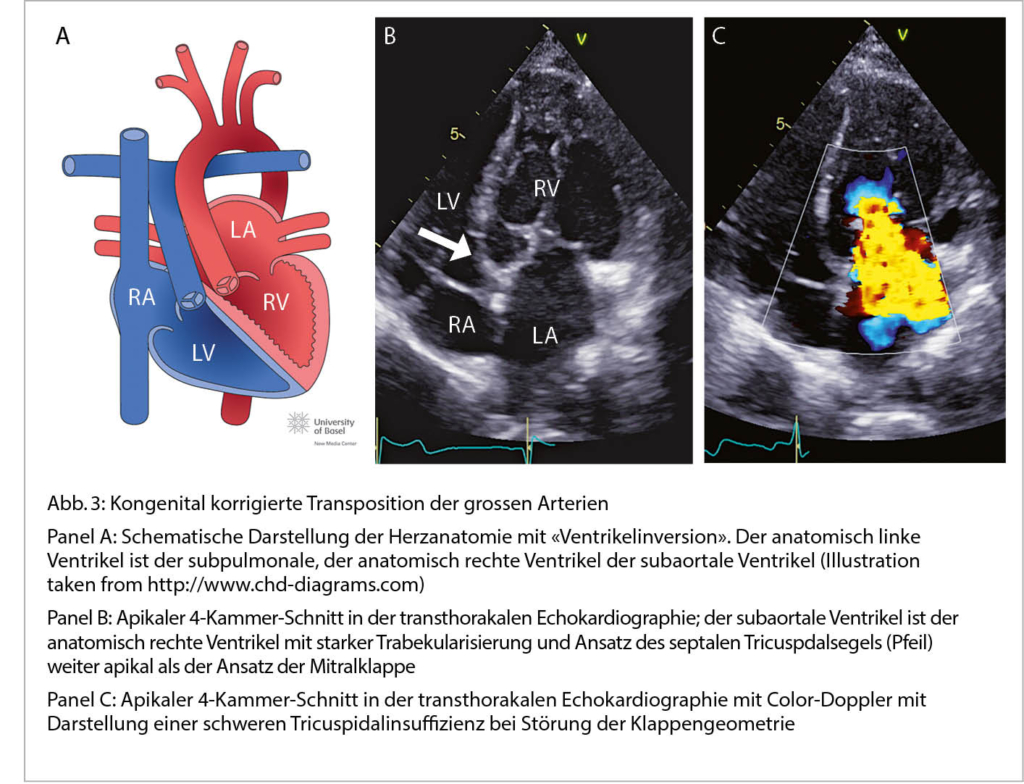

Kongenital korrigierte Transposition der grossen Arterien

Die Ursache der kongenital korrigierten Transposition der grossen Arterien ist eine fehlerhafte «Faltung» des Herzschlauches während der Embryonalentwicklung. Durch den L-loop kommt es physiologisch zur «Ventrikelinversion». Das heisst, der rechte Vorhof

konnektiert zum morphologisch linken Ventrikel, der linke Vorhof zum morphologisch rechten Ventrikel. Die Pulmonalarterie entspringt dem subpulmonalen linken, die Aorta dem subaortalen rechten Ventrikel (Abb. 3). Wenn zusätzliche Defekte vorliegen (am häufigsten sind Ventrikelseptumdefekte und die Pulmonalstenose) erfolgt die Diagnose meist im Kindesalter. Bei Fehlen zusätzlicher

Defekte wird die Diagnose gelegentlich erst im Erwachsenenalter gestellt. Dann meist bei Auftreten von Komplikationen (progrediente Tricuspidalinsuffizienz, Herzinsuffizienz oder atrioventrikulärer Block). Die Betreuung solcher Patienten sollte in Zusammenarbeit mit einem spezialisierten Zentrum erfolgen.